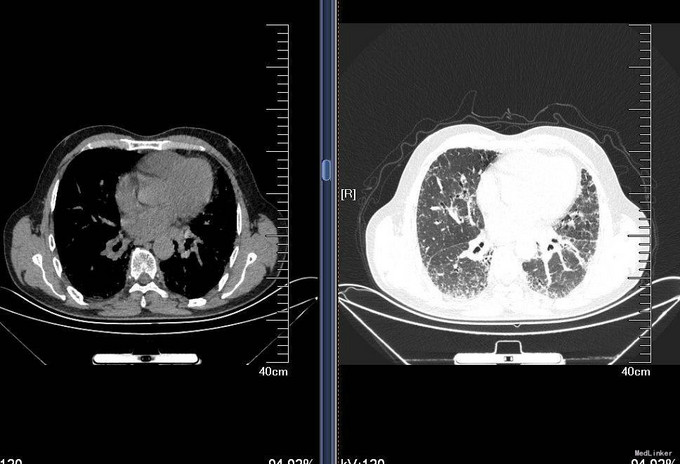

查体:T36.5℃,P 80次/分,R 18次/分,BP 120/80mmHg,神清语明,查体合作,周身皮肤无黄染及出血点。巩膜无黄染,结膜无苍白,球结膜无水肿,口唇无发绀,颈静脉无充盈,颈部浅表淋巴结未触及。双肺呼吸音粗,未闻及干湿性啰音,心音钝,律齐,各瓣膜听诊区未闻及病理性杂音。腹平软,无压痛,无反跳痛及肌紧张,未触及包块。肝肋下未触及,双肾区无扣痛,移动性浊音阴性。双下肢无水肿。 入院后完善肝肾功离子,血气分析,血常规,CRP,支原体抗体,肺通气功能,弥散功能等检查,检验回报:血常规:白细胞计数 9.710^9/L;中性粒细胞百分比 46.8%;红细胞计数 4.6810^12/L;血红蛋白 148g/L;血小板计数 21310^9/L;CRP:C-反应蛋白 <3.28mg/L;肺炎支原体抗体:肺炎支原体抗体 阴性(-); 肺通气功能:FEV1/FVC:90,%Pre:78%,混合性通气功能障碍,以限制为主;支气管舒张试验试验:支气管舒张试验阴性,FEV1改善率1%,增加30ml;弥散功能:总弥散量中度下降,单位弥散量正常;胸部HRCT:双肺弥漫性间质性肺炎。 双侧胸膜局部增厚。